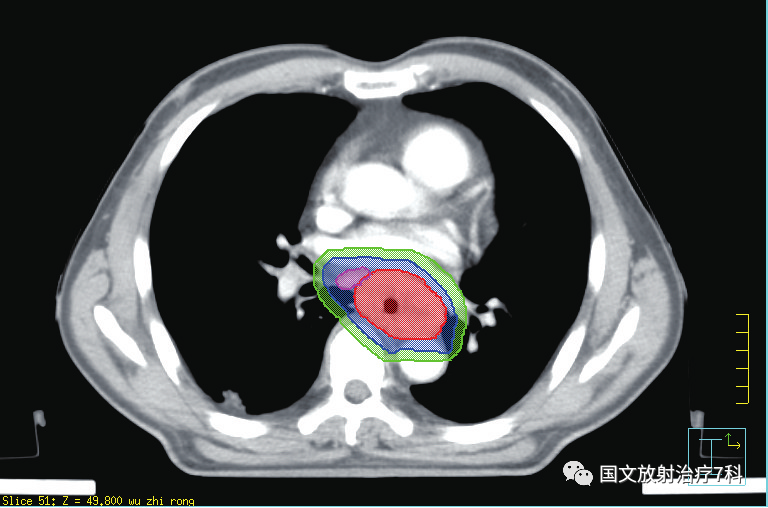

第二步,CT模擬定位。在扣膜狀態(tài)下進行CT平掃+增強掃描,獲取影像后放療科醫(yī)生就可以在電腦上借助軟件進行靶區(qū)的勾畫了。

第三步,勾畫靶區(qū)之后,醫(yī)生需要提交治療計劃,與醫(yī)學物理師共同完成對靶區(qū)劑量的設定,以及危及器官受量的限定。物理師需要借助電腦軟件精確腫瘤患者的放療物理范圍,獲得最優(yōu)的物理劑量分布,做出一個讓放療醫(yī)生滿意的放射治療方案,為腫瘤患者“對癥下藥”。 簡單來講,就是讓射線最大量的照射在靶區(qū)上,最大程度地控制周邊需要保護器官的射線劑量。靶區(qū)勾畫和治療計劃確認依病情的復雜程度一般需要3-7天,需要患者的耐心等待。醫(yī)學物理師是臨床醫(yī)師和大型精密治療器械的銜接單位,有強大的醫(yī)學物理師團隊是對治療的充分保障。